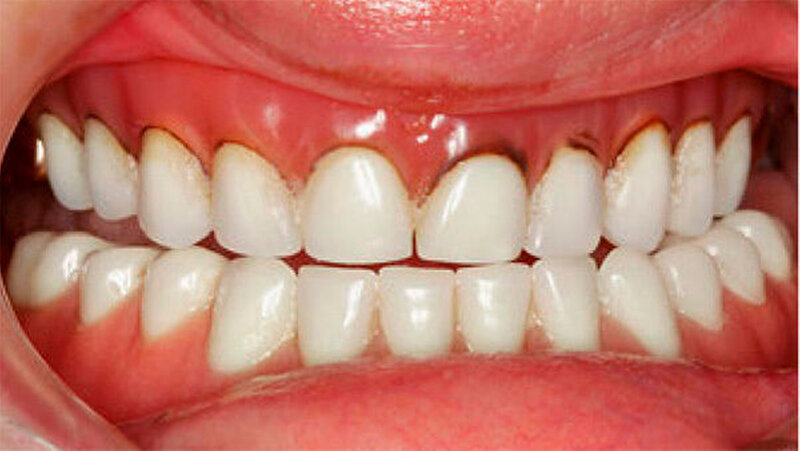

Der bei Behandlungsbeginn 14-jährige Patient war mit einer neun beziehungsweise fünfjährigen Prothese im Unter- beziehungsweise Oberkiefer versorgt (Abb. 2 und 3). Die angelegten Zapfenzähne 12, 11 und 21 waren bereits mehrfach konservierend restauriert und wiesen diverse Stellen mit Sekundärkaries auf. Die Kronenränder der Zähne 33 und 43 waren deutlich sondierbar. Der Kieferkamm im Unterkiefer war aufgrund der fehlenden Zahnanlagen sehr schmal (Abb. 4 bis 6). Die Panoramaschichtaufnahme zeigte das reduzierte vertikale Knochenangebot (Abb. 7). Da die Vitalerhaltung der wenigen Restzähne aufgrund des jungen Alters des Patienten unbedingt anzustreben war, wurde als Behandlungsziel im Ober- und Unterkiefer eine Versorgung mit Hybridprothesen, retiniert auf Teleskopkronen, festgelegt.

Die Patientin war mit einer knapp neunjährigen Teilprothese im Ober- und einer zweijährigen Totalprothese im Unterkiefer versorgt. Beim Lachen wurden die nicht mehr altersentsprechenden Prothesenzähne mit den deutlichen Randverfärbungen ersichtlich (Abb. 19). Das sagittale Wachstum des zahnlosen Unterkiefers führte in den letzten zwei Jahren aufgrund der verstärkten Kontakte im Frontzahnbereich zu einer beidseitigen Nonokklusion im Seitenzahnbereich (Abb. 20). Eine rasche Verbesserung der Ästhetik als auch der Funktion war unbedingt angezeigt, um das Selbstbewusstsein dieses puberalen Mädchens zu stärken.